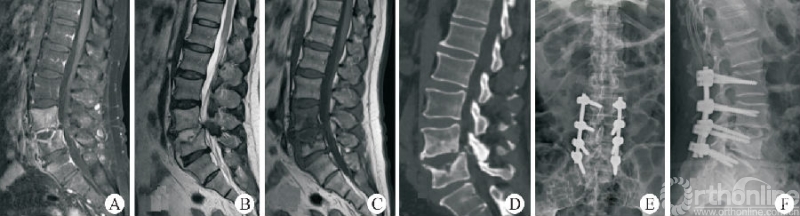

3.2 Stand⁃alone OLIF

尽管经典的OLIF手术能够有效解决众多腰椎失稳性疾病,但是术中变换体位、二期手术等因素限制了其应用。Stand-alone OLIF(图5)的概念也应运而生,Stand-alone OLIF能够避免椎旁肌肉等软组织的损伤,对于改善术后因肌肉剥离等引起的腰背部疼痛有一定的意义。

图5 Stand-alone OLIF

生物力学试验证明,侧方融合器可以有效重建脊柱的稳定性,也为Stand-Alone OLIF提供了理论依据[30-31]。ZHU等[32]通过比较Stand ⁃alone OLIF与PLIF两种手术方式治疗邻椎病,发现OLIF组术中出血量少,手术时间短,卧床休息时间短,住院时间短,且都能获得满意的融合效果。

UDBY等[33]回顾性研究对比Stand-alone前路融合与联合后路钉棒固定两种手术方式,结果发现,Stand-alone技术在ODI、VAS、手术时间、失血量和患者满意度等方面有显著优势。MANZUR等[34]回顾性分析了Stand-alone前路融合的融合率为88.6%,总体上获得了较高的融合率。因此,Stand-alone OLIF是一种有效的椎体间融合术式,且具有手术时间短、出血量少、患者满意度高、术后疼痛轻等优势。对于合适的患者选择Stand-alone OLIF,既能获得满意的疗效,又能尽可能减小损伤。

但是Stand-alone OLIF有其应用边界。对于骨密度降低[35]、术中终板损伤,术中前纵韧带损伤、冠状面失衡(C7铅垂线距离骶骨正中线>2cm)、动力位X线片显示动态不稳(过伸过屈位节段位移>3mm或角度变化>11°)、Ⅱ度退行性滑移、矢状面失衡(C7铅垂线距离骶骨后上角>2.5cm)、峡部裂滑移、邻椎病发生在原有融合节段远端、融合节段≥3个、Ⅱ~Ⅲ度关节突关节骨关节炎(关节突关节间隙狭窄,伴关节突明显增生肥大、硬化、骨赘增生、关节面破坏)等患者,建议联合内固定,以增强稳定性、降低翻修等的风险。

终板塌陷和融合器沉降(图6)是Stand-aloneOLIF的常见并发症,也是导致术后翻修的重要预测因素。融合器沉降与终板强度、手术操作以及解剖稳定性相关。终板硬化及形态平衡能够降低融合器沉降的发生率[36]。

图6 OLIF术后融合器沉降

LIU等[37]研究发现,在MRI影像中有Modic改变以及CT影像提示终板硬化的患者终板沉降的发生率明显低于其他患者。术中选择合适的融合器以及良好的脊柱稳定性也有利于降低融合器沉降的发生率[38]。ZHANG等[30]研究利用尸体标本模拟OLIF手术,通过研究生物力学特征、骨小梁微结构损伤等探索融合器与椎体骺环相对大小及位置对终板塌陷及融合器沉降发生率的影响,因此,在Stand-alone OLIF中选择合适的融合器对于减少终板塌陷及融合器沉降至关重要。

FANG等[39]通过构建有限元模型比较Stand-alone OLIF与OLIF联合后路钉棒系统固定两种手术方式后屈伸活动时终板应力等的变化,发现OLIF联合后路钉棒系统可降低屈伸活动时终板所承受的最大应力。术中终板损伤、间隙过度撑开等均会增大融合器沉降的发生风险。